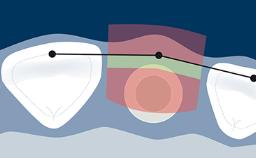

These investigations are used to assist in the diagnosis of pathology, aid in implant treatment planning, and monitor peri-implant bone levels on maintenance assessments, such as this image taken at a 1-year follow-up visit.

To achieve these goals, radiographic images need to meet basic standards of quality.

They need to have sufficient density and contrast to clearly show changes and to demonstrate sharp detail. Distortion, blurring from movement, and other artifacts limit a radiograph's diagnostic value.